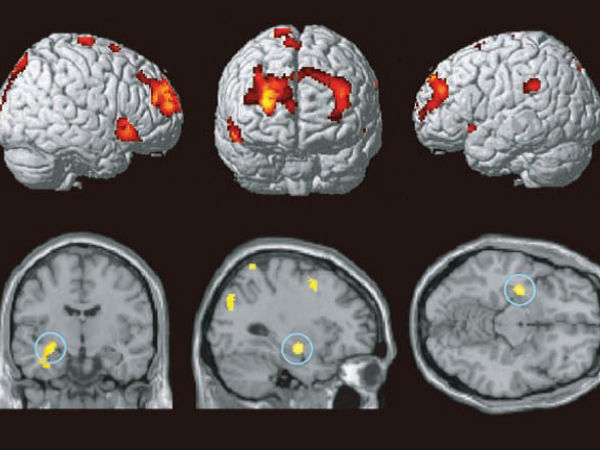

மூளை வலிமை :

ஒவ்வொரு முறையும் எதையாவது நினைவுப்படுத்தும் போது, நமது மூளையானது வலிமையடைகிறது. மேலும் இடையே நுழையும் சம்பந்தமில்லாத நினைவுகள் கவனச்சிதறலை ஏற்படுத்தும்.

நீடித்த நினைவக சுவடு சக்தி :

அப்படியாக சாதரணமாக நினைவுப்படுத்தும் போதே நாம் திசை மாற வாய்ப்புகள் அதிகம் என்கிற போது எப்போதுமே மொபைல்போன் அல்லது கணினி அல்லது இன்டர்நெட் மூலம் தகவல்களை கண்டறிந்து தெளிந்துகொள்ளும் பழக்கம் ஆனது நம் திடமான மற்றும் நீடித்த நினைவக சுவடு சக்தியை முற்றிலுமாக அழித்துவிடும்.